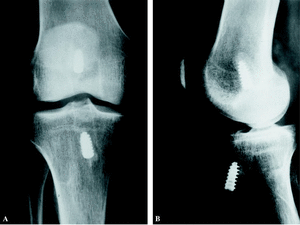

Veintiocho pacientes refirieron crepitaciones femoropatelares, que sólo en 6 casos fueron dolorosas, y que cedieron con antiinflamatorios y modificación de la pauta de rehabilitación. No se observaron cambios radiológicos degenerativos en ninguno de los compartimentos de la rodilla. (fig. 3). Ninguno de los pacientes de esta serie tuvo que ser reintervenido a posteriori por lesiones meniscales o condrales. No se observaron infecciones de la herida quirúrgica ni de la articulación. Tampoco se evidenciaron trombosis venosas de las extremidades inferiores.

Figura 3. A: Radiografía anteroposterior de una rodilla 5 años después de la reconstrucción del LCA. Nótese la ausencia de cambios radiológicos. B: Radiografía lateral de la misma rodilla.